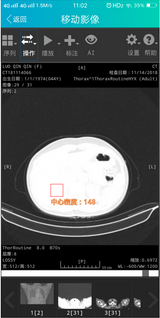

日前我们获悉,这一现状或许会有一些改变。近日。芯联达公司微信公众号便发布了新推出纷享云影像和移动影像两款产品。据悉,紛享医疗平台新推出的纷享云影像和移动影像服务已成功在2018年落地近二十家公立医院和五十余家基层医疗机构。芯联达公司董事长杨宏桥博士告诉记者,除了新发布的产品之外,芯联达还正致力于研发5G下的新一代移动医疗应用平台。

据了解,紛享云影像是以医疗影像智能处理技术为手段,以紛享医疗平台数年积累的海量医疗数据为依托打造的专业医学影像智能处理平台;而移动影像则是在此基础上进行的移动端应用延伸。这两款产品从实用场景层面弥补了诸多现有缺失,可以预见,在未来一段时间,医疗影像AI的应用将迎来大面积的铺开。